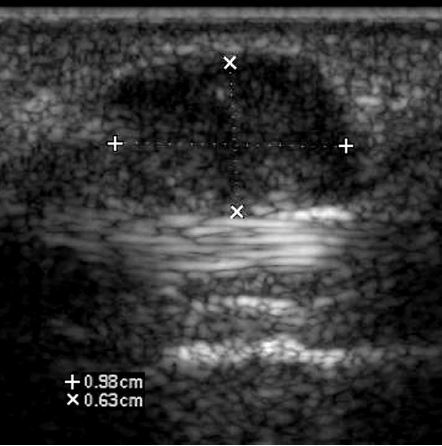

Longitudinal gray-scale and color Doppler views of the thumb in a patient with a palpable mass along the volar surface.

• 2nd most common mass lesion in the hand (most common = ganglion cyst)

• solid with internal vascularity

• intimately associated with tendon sheath

• a benign disorder of proliferative synovium arising from the tendon sheaths

• histologically identical to PVNS

• women > men